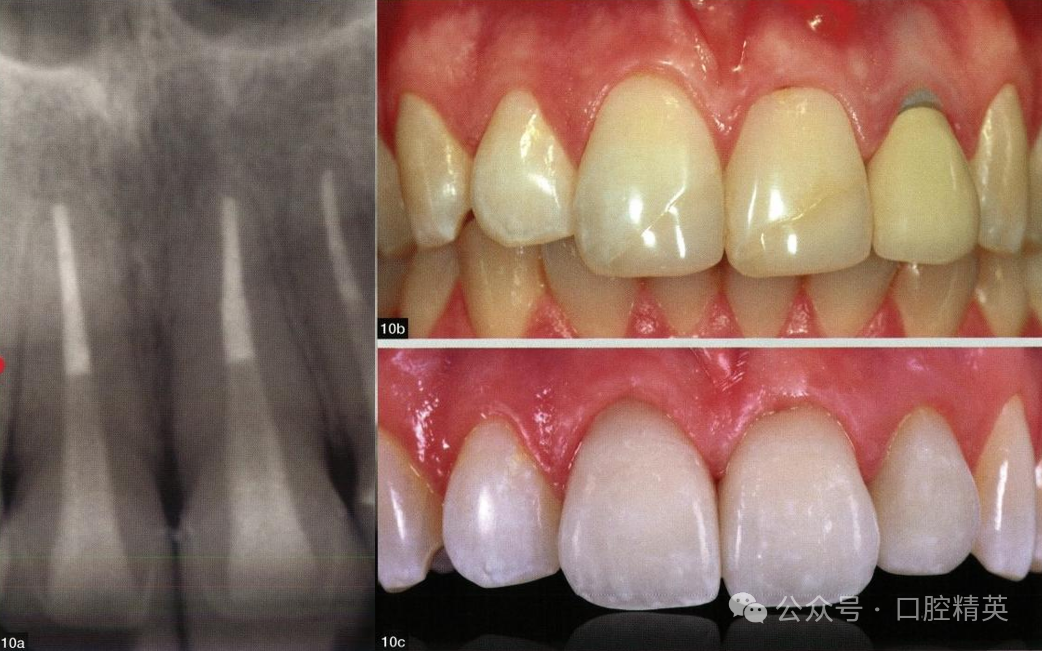

图:10a~c 根管治疗后牙齿的 修复方案既要方便再治疗,又 要满足功能和美观需求。